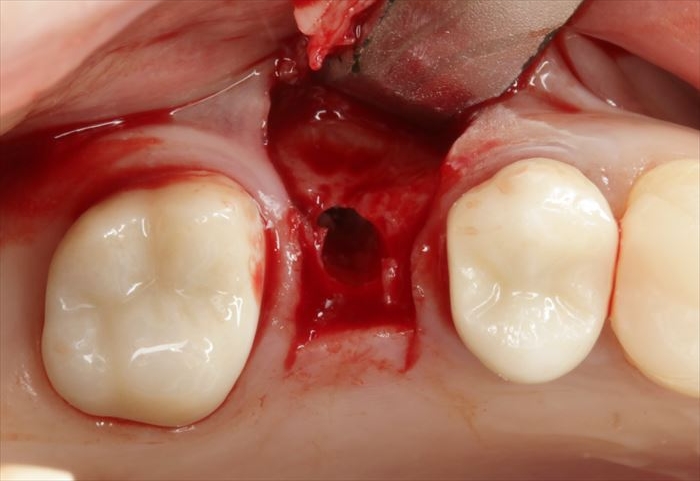

ドリルサイズを拡大してドリリングを終えました。

実際の骨の形を確認するために粘膜を剥離します。

頬側骨が少々足りない状況ですので、インプラント埋入後に骨増生処置(GBR)を行います。